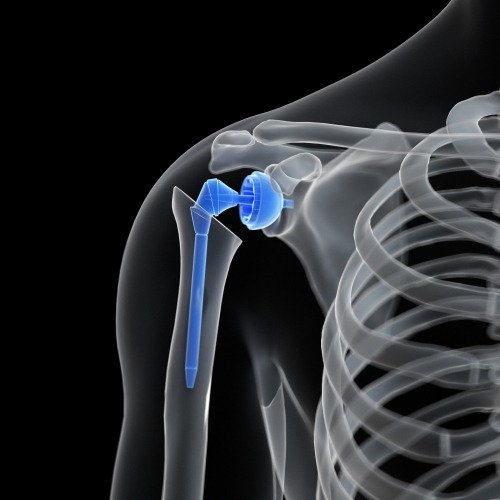

Shoulder instability happens when the shoulder joint’s lining, labrum, or ligaments become torn, stretched, or detached. This allows the humeral head or the ball of the shoulder joint to move partially or completely out of the socket. Individuals with this type of instability feel pain when the shoulder is not in its place.

Shoulder tendinitis and bursitis are common reasons for pain and stiffness in the shoulders. These involve inflammation or swelling in a particular area within the shoulder joint. Rotator cuff, a group of muscles, along with the bicep tendon keep the shoulder joint stable. These tendons and muscles keep the humerus or the upper arm bone within the glenoid or the shoulder socket.

Shoulder is comprised of several joints, tendons, and muscles that allow for a wide range of motion in the arm region. You can do everything from throwing the perfect pitch to scratching your back. However, mobility comes at a price. It may lead to impingement or instability in the bony structure or soft tissue in the shoulder, causing pain.